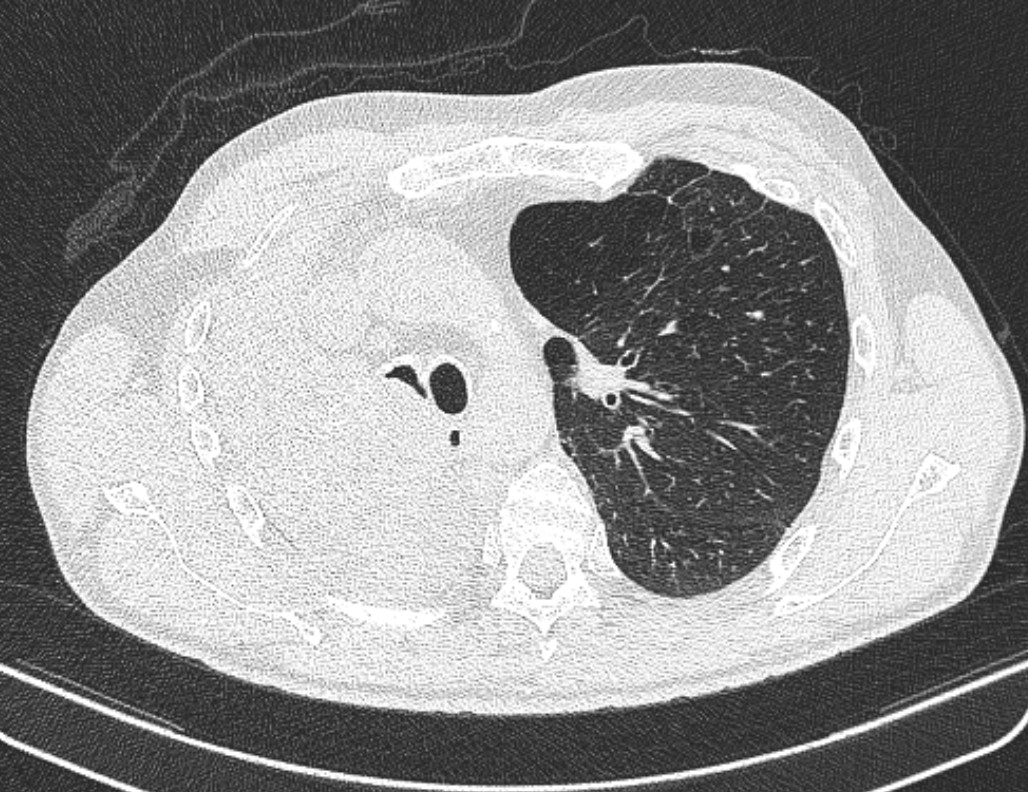

- გულმკერდის კტ აქსიალურ ჭრილში სტენტირების დღეს.